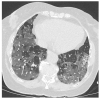

COVID-19-associated pulmonary aspergillosis (CAPA) is a recently described disease entity affecting patients with severe pulmonary abnormalities treated in intensive care units. Delays in diagnosis contribute to a delayed start of antifungal therapy. In addition, the emergence of resistance to triazole antifungal agents puts emphasis on early surveillance for azole-resistant Aspergillus species. We present a patient with putative CAPA due to Aspergillus fumigatus with identification of a triazole-resistant isolate during therapy. We underline the challenges faced in the management of these cases, the importance of early diagnosis and need for surveillance given the emergence of triazole resistance.